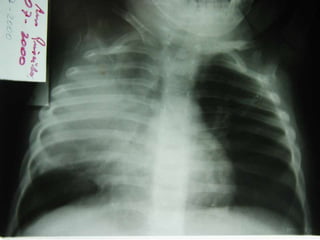

•Edad 6 años

•Tos de 1 año

•Falta de apetito

•PPD: 10 mm

Criterios Radiológicos

diagnóstico